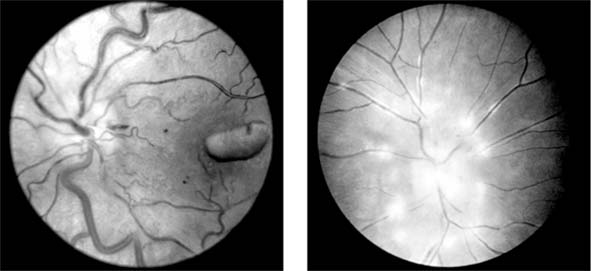

Central Retinal Vein Occlusion (new window  Figure 15-7)

Figure 15-7

Figure 15-7: Central retinal vein occlusion. Left: Photograph shows linear hemorrhages in the nerve fiber layer and punctate hemorrhages in the deeper retinal layers. Right: Fluorescein angiogram shows dilation of the veins.

Fundus examination shows dilated tortuous veins with retinal and macular edema, hemorrhages all over the posterior pole, and cotton-wool spots. The arterioles are usually attenuated, indicating generalized microvascular disease.

The prognosis for vision is poor. Fluorescein angiography demonstrates two types of response: a nonischemic type, with dilation of retinal vessels and edema; and an ischemic type, with large areas of capillary nonperfusion or evidence of retinal or anterior segment neovascularization. In 93% of ischemic and 50% of nonischemic central retinal vein occlusions, the ultimate visual acuity is less than 20/200.

Central retinal vein occlusion has an increased incidence in certain systemic conditions such as diabetes mellitus, hypertension, collagen vascular diseases, and hyperviscosity syndromes (eg, Waldenström's macroglobulinemia, angioimmunoblastic lymphadenopathy). However, the prevalence of cerebrovascular or cardiovascular disease is not increased compared to the general population. Investigations include measurement of serum lipids, plasma proteins, plasma glucose, and assessment of blood viscosity by hemoglobin, hematocrit, and fibrinogen estimations. In young patients, protein C, activated protein C resistance, protein S, and antithrombin III levels should be measured to exclude abnormalities of the thrombolytic system. If hypertension is present, simple renal function tests, including urea and electrolytes, estimation of creatinine clearance, microscopic examination of the urine, and renal ultrasound are indicated.

Treatment of retinal vein occlusion is unsatisfactory. Trials with anticoagulants and fibrinolytic agents have not been successful. In ischemic central retinal vein occlusion, panretinal laser photocoagulation is effective in preventing and treating secondary neovascular glaucoma.

Occasionally, central retinal vein occlusion occurs in young people and may be associated with cells in the vitreous. Rheologic investigations are usually negative, and the prognosis for vision is good.